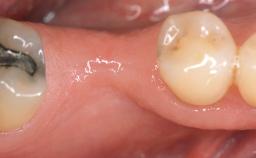

Early Implant Placement, Contour Augmentation, and Autologous Connective-Tissue Graft Using a Tunneling Technique to Replace an Upper Incisor with Generalized Gingival Recession

Variations in soft-tissue volume, evidenced either by an overabundance (Evian and coworkers 1993; Levine and McGuire1997; Dolt and Robbins 1997) or by a deficiency of soft or hard tissue can complicate implant-supported rehabilitations in the esthetic zone (Lorenzana 2008; Lorenzana and coworkers 2009). The present case illustrates the replacement of a failing upper left lateral incisor complicated by generalized severe gingival recession in the esthetic zone.